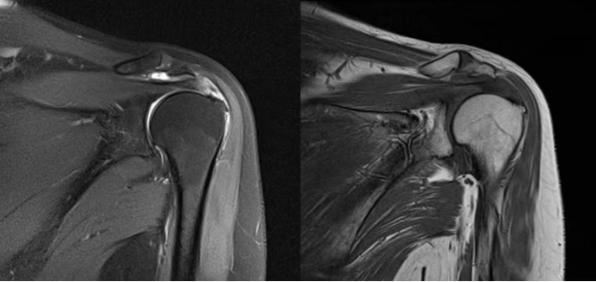

(4)MRI:行MRI检查出现肩关节韧带损伤、肿胀、撕裂可确诊;